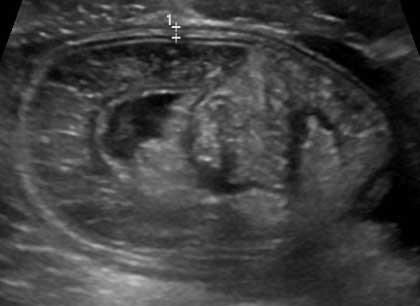

A 3-year-old boy is brought to the emergency department due to abdominal pain.  The pain began several hours ago and comes and goes.  During these episodes, he holds his belly, screams, and draws up his legs.  He has had nonbloody, nonbilious vomiting 3 times since the last painful episode.  Between the episodes, the patient has no pain and is playful.  His last bowel movement was yesterday and was normal.  Two weeks ago, he had gastroenteritis that resolved after 3 days.  He otherwise has no chronic medical conditions and takes no medications.  Temperature is 37.2 C (99 F) , blood pressure is 95/50 mm Hg, and pulse is 100/min.  Abdominal examination shows a soft abdomen that is tender with voluntary guarding to palpation at the right upper and lower quadrants.  Rectal examination reveals no fissures or hemorrhoids.  The remainder of the examination is normal.  Ultrasound of the abdomen is shown in the image below: A 3-year-old boy is brought to the emergency department due to abdominal pain.  The pain began several hours ago and comes and goes.  During these episodes, he holds his belly, screams, and draws up his legs.  He has had nonbloody, nonbilious vomiting 3 times since the last painful episode.  Between the episodes, the patient has no pain and is playful.  His last bowel movement was yesterday and was normal.  Two weeks ago, he had gastroenteritis that resolved after 3 days.  He otherwise has no chronic medical conditions and takes no medications.  Temperature is 37.2 C (99 F) , blood pressure is 95/50 mm Hg, and pulse is 100/min.  Abdominal examination shows a soft abdomen that is tender with voluntary guarding to palpation at the right upper and lower quadrants.  Rectal examination reveals no fissures or hemorrhoids.  The remainder of the examination is normal.  Ultrasound of the abdomen is shown in the image below:   Which of the following is the best next step in management of this patient? A) Air enema B) CT scan of the abdomen C) Exploratory laparotomy D) HIDA scan E) Technetium-99m pertechnetate scan Which of the following is the best next step in management of this patient?